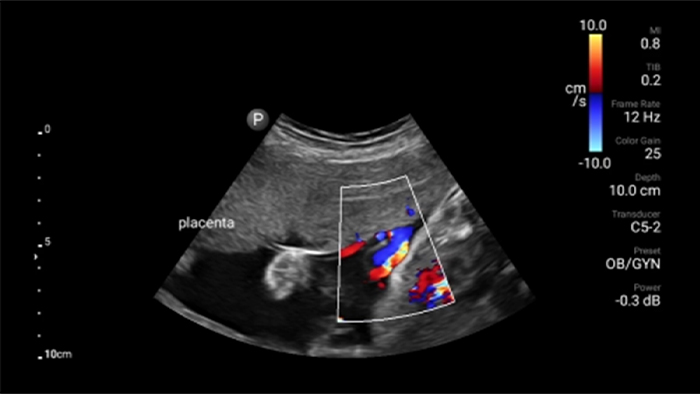

Lumify kan helpen de subtiele details van een beeld zichtbaar te maken en afwijkende weefselstructuren bloot te leggen vanuit verschillende hoeken. Hierdoor kunt u met vertrouwen realtime beslissingen nemen, van diagnose tot herstel.